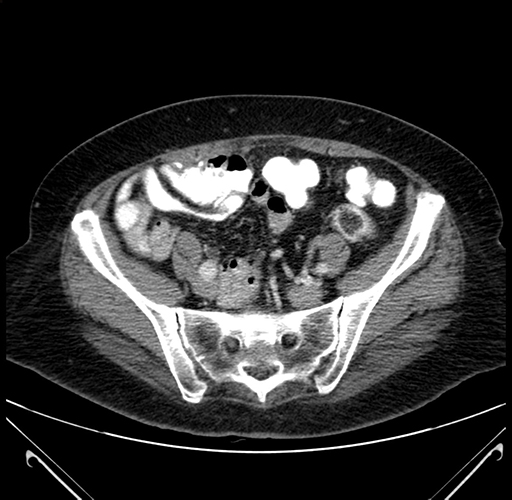

Pre-Chemo: Axial Venous

Axial Venous